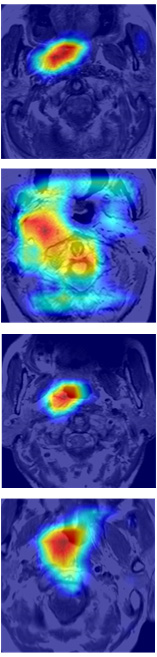

Some examples of spatial attention coefficients are shown in Figure 11. We can see that, several locations may fire at the beginning of training phase and then energy will slowly build up over ROIs and reduce the attention to false positives.